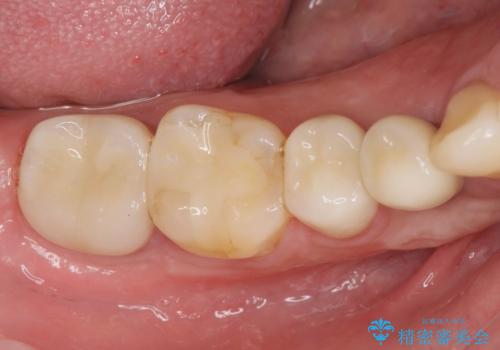

- 過去、多数の部位の虫歯治療を受けこれまで再発を繰り返してきたことから「徹底的な虫歯治療を受けたい。」と希望され来院されました。

虫歯の大きさから保存できなかった歯はインプラント治療を行い、その他の歯は虫歯のステージに合わせて根管治療、セラミックインレー、 セラミッククラウンを精密に行うことで長期的な予後を期待できる状態へと治療を進めます。

- 34.1万円(ジルコニアクラウン×2・仮歯×2・セラミックインレー×1・インプラント治療を除く)費用は治療当時の料金となります